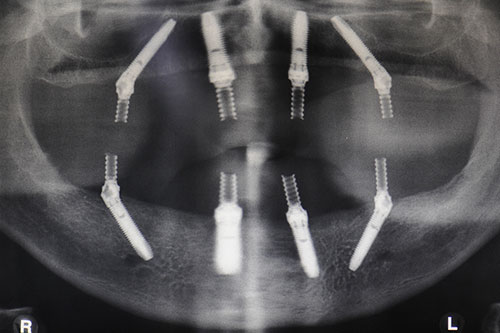

Az IHDE fogászati fogászati implantátumai megfelelnek minden nemzetközi minőségi elvárásnak, és bizonyítvánnyal is rendelkeznek, amely garantálja az IHDE fogászati implantátumok biztonságos használatát bármely országban, így már hazánkban is elérhető, csakis nálunk, a fog-ma.hu weboldalon.

Implantációs fogpótlás elérhető nagyon alacsony áron csakis a fog-ma.hu weboldalon, ezért érdemes hozzánk fordulni ha önnek is problémái vannak, hiszen az implantációk hosszútávú megoldást jelentenek, ráadásul olcsóak is. IHDE fogászati implantátumokat közel 20 éve készítik azért, hogy csökkentsék a kezelési időt, ami sikerült is, hiszen a néhány  éves kezeléseket mindössze néhány naposra csökkentették. A fogászati és szájsebészeti beavatkozásokon jelentősen támaszkodnak az azonnali terhelés módszerére, ez pedig már nagyon régóta hatásosnak bizonyul. Az implantátumok általában egyetlen darabból, egy csavarból állnak és nincs összekötő elem a mesterséges gyökér és a szuprakonstrukció (korona vagy híd) között, ami problémákat okozna.